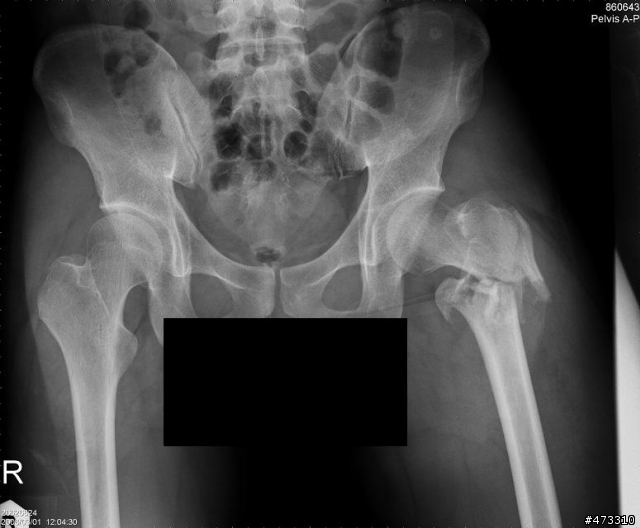

小的我真正重傷害的是在大腿部位

股骨頸與股骨幹本體分離

外加小轉子在復位手術後脫離股股本體跑到坐骨附近

問醫生說阿能處理嗎?他說很難

因為那位置有大量神經叢還有韌帶

大腿總圖

斷裂處特寫

復位手術後兩個月的樣子,有看到一個碎片掉進去坐骨的位置了嗎?